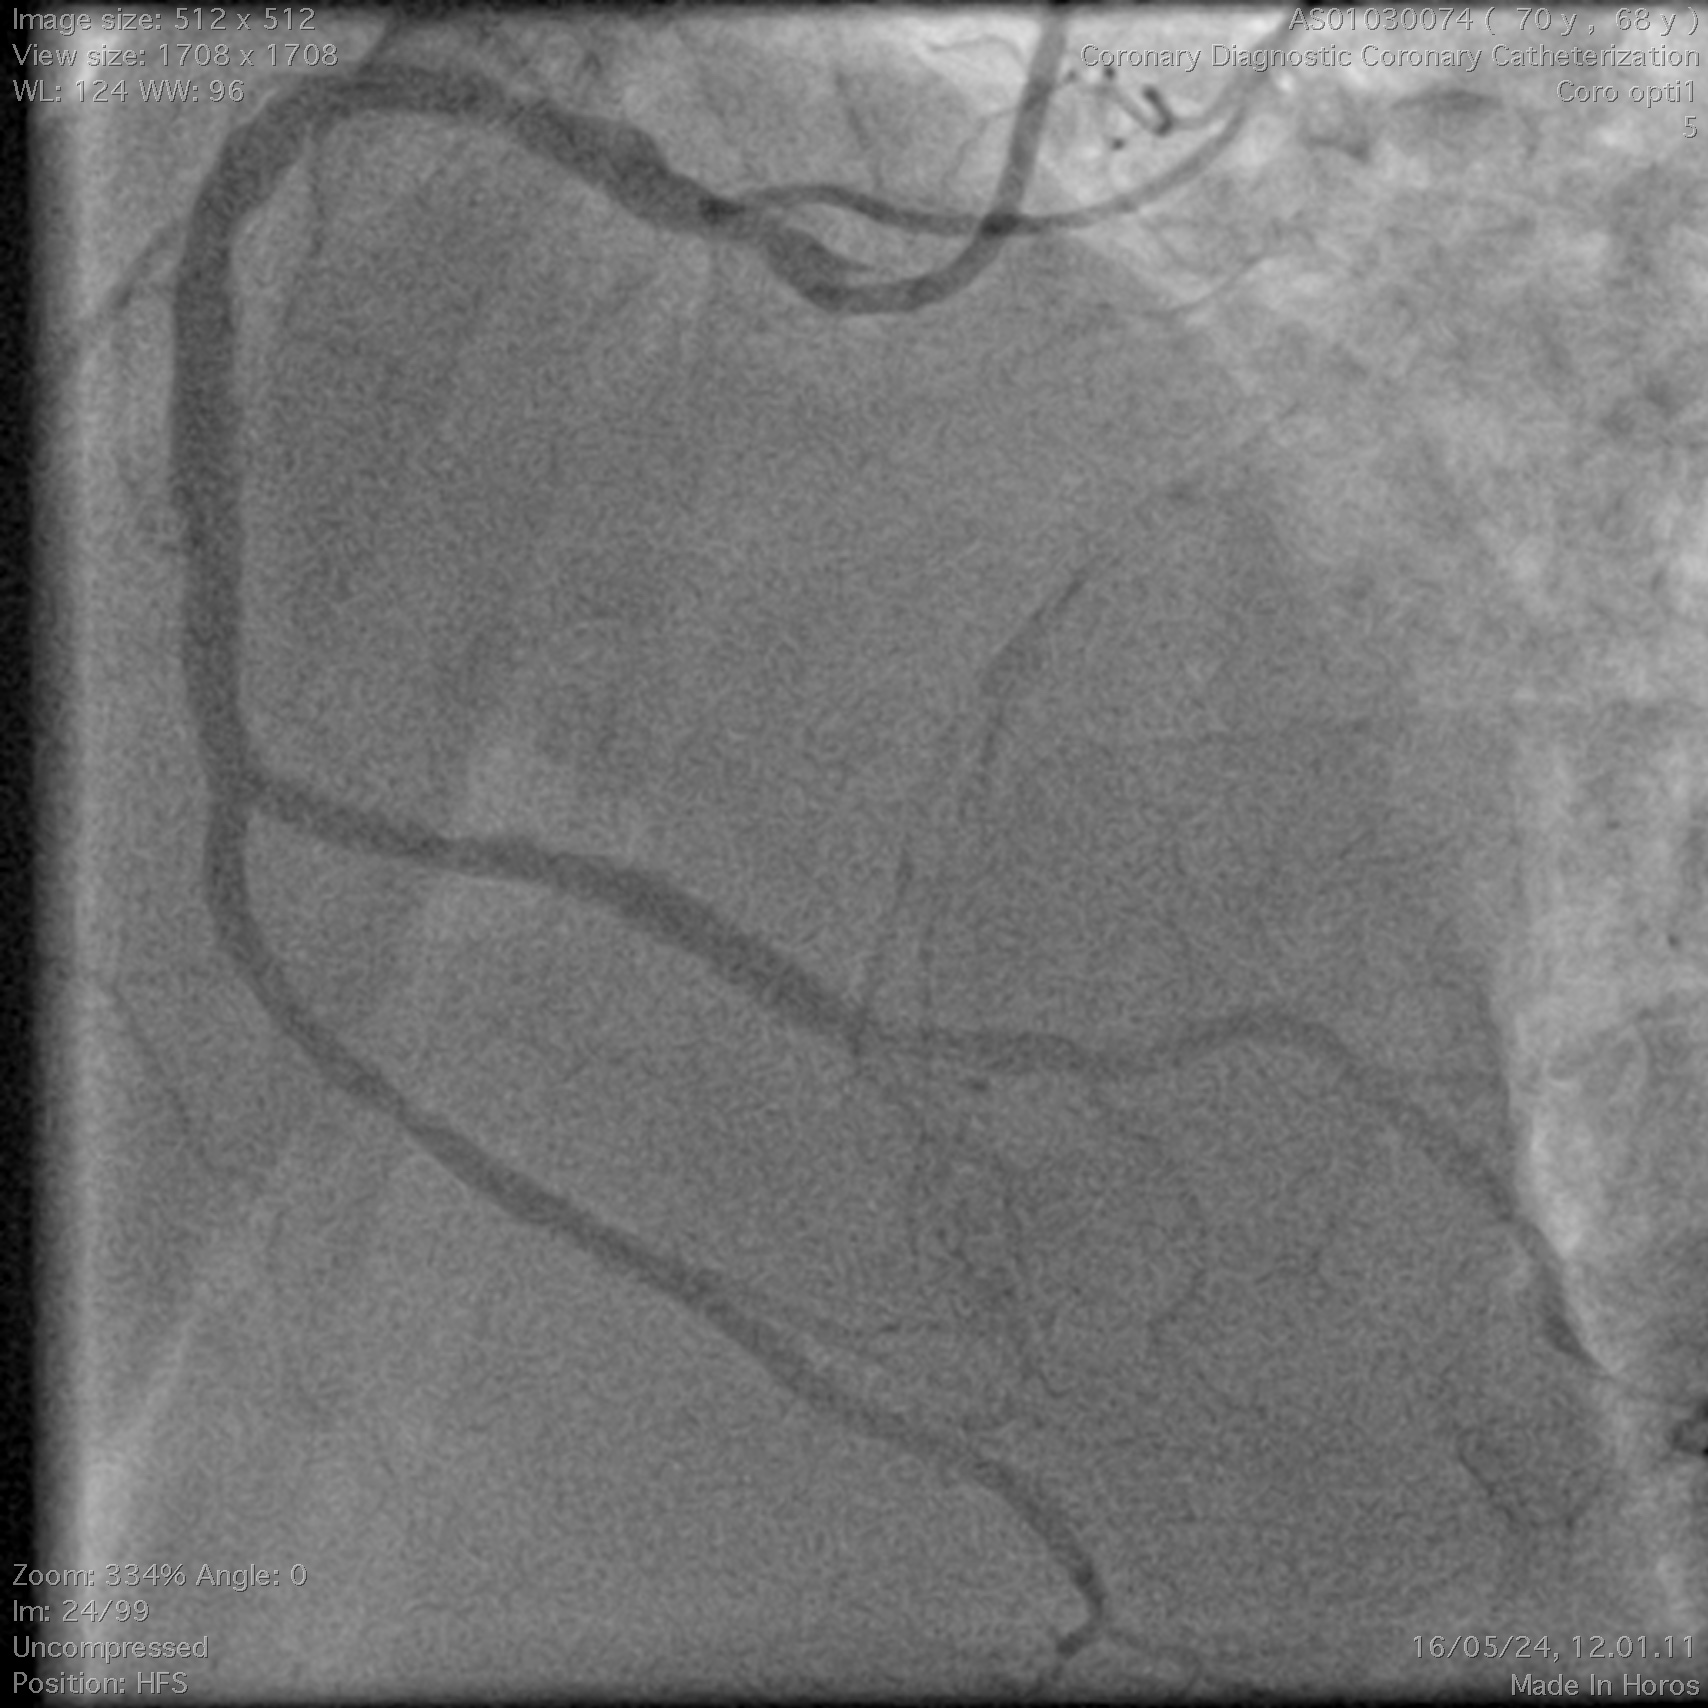

Coronary angiography demonstrated a right-dominant system with significant ostial LCx stenosis and a blunt ostial LAD chronic total occlusion, with a J-CTO score of 4. The RCA showed mild coronary disease and supplied collateral flow to the LAD territory, graded as Werner CC2.

Through bilateral femoral access, 7Fr EBU 3.5 and JR 4.0 catheters were engaged to the left main and RCA. With no antegrade entry, a retrograde marker wire and IVUS-guided antegrade puncture using Gaia Next 2 and Conquest Pro with Finecross failed, as both wires were deflected by the calcified cap despite tip modification with a secondary curve. A retrograde attempt using Gaia Next 2 and 3 with Finecross also failed.Suspecting LAD angulation, an antegrade re-attempt was performed using IVUS-guided puncture with a Conquest Pro 8-20 supported by a Supercross90 under retrograde wire guidance, successfully puncturing the proximal cap. Supercross was exchanged for Finecross, and the wire crossed distally, but Finecross and Corsair Pro XS could not advance due to the tight lesion. After proximal preparation and the anchor balloon technique in the LCx, the microcatheter advanced distally and the wire was exchanged for a workhorse wire. Retrograde injections confirmed true lumen position, and the LAD was predilated. IVUS showed mixed plaque and myocardial bridging in the mid LAD and mixed plaque at the ostial LCx. Further preparation was performed with a 3.5 mm scoring balloon. A hybrid strategy using a 4.0¡¿20 mm DCB for the LCx and a 4.0¡¿32 mm DES from LM to LAD, followed by 5.0 and 4.0 NC balloons for post-dilatation, achieved final TIMI 3 flow without complications.